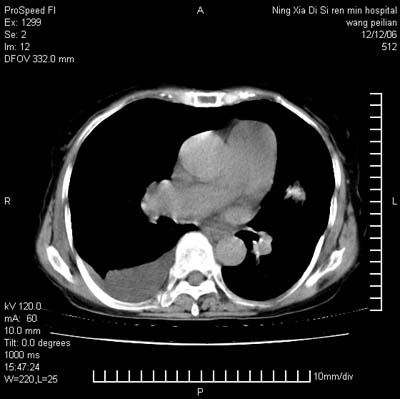

标题: CT5609:胸部:女77 病史不详 [打印本页]

标题: CT5609:胸部:女77 病史不详

两肺可见多个大小不等的结节,左侧有胸水,纵隔淋巴结增大,考虑是细支气管肺泡癌

两肺尖纤维索状影,两下肺结节块状影,且有钙化灶,右胸腔积液。考虑肺结核并胸膜炎。

两肺尖纤维索状影,两下肺结节块状影,且有钙化灶,右胸腔积液。考虑肺结核并胸膜炎肺间质纤维化

考虑:1、慢性支气管炎合并全小叶型肺气肿、间质纤维化;

2、双肺结核;

3、右侧胸膜炎(积液)。

1、双肺继发型肺结核(以纤维、增殖灶为主);

2、右侧胸腔积液;

3、其余符合老年肺改变。

双肺见多个结节状及条索状影,双侧胸腔积液,右侧叶间积液,考虑结核性胸膜炎